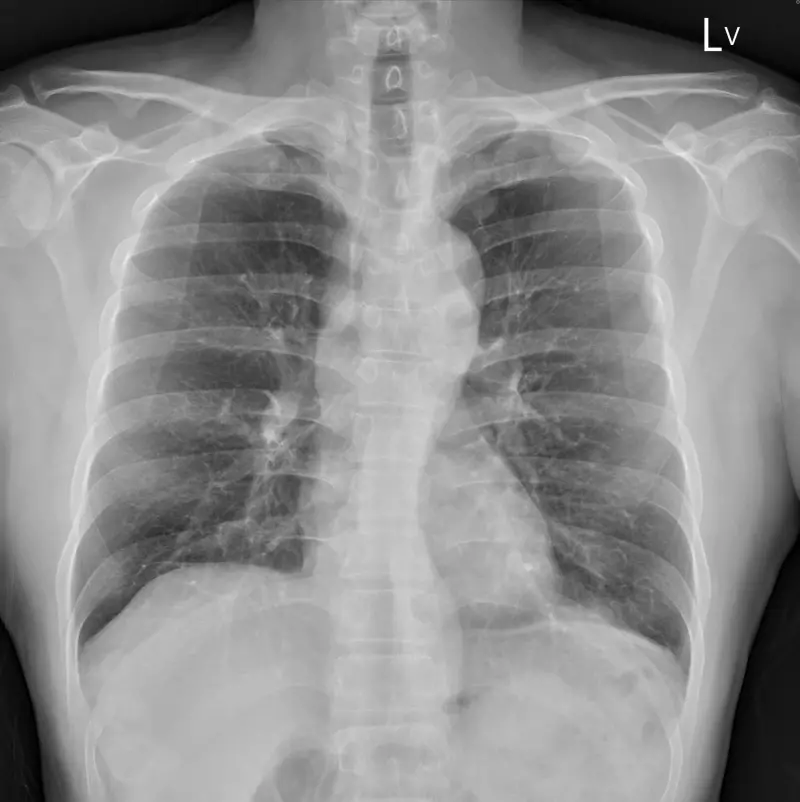

蘇一峰先在文中放上X光圖,讓網友看看腫瘤,並在留言處附上圈起的腫瘤示意圖「躲在主動脈裡面,五公分縱膈腔腫瘤」,讓網友也紛紛回應「好可怕,跟空污有絕對關係」、「好可怕的無症狀」、「癌症讓人難受的是人生突然被畫下句點」。

▲一名4旬男沒有任何不舒服,健檢去年正常、今年卻發現已癌末。(圖/翻攝自蘇一峰臉書粉專)